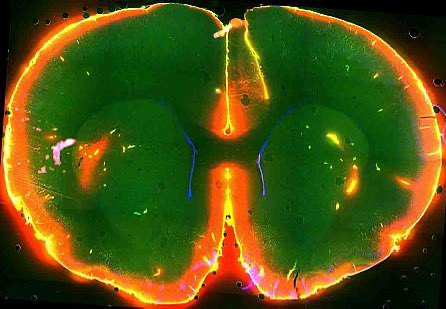

هذه أول صور تظهر للمجتمع العلمي على الإطلاق ، فعندما ننام ، تغسل موجات السائل النخاعي فوق الدماغ لإزالة (الأفكار السلبية).

بعد بضع ثوان ، سيتدفق الدم من رأسك. بعد ذلك ، سيتدفق سائل مائي يسمى السائل النخاعي (CSF) ، ويغسل عبر دماغك بموجات إيقاعية نابضة.